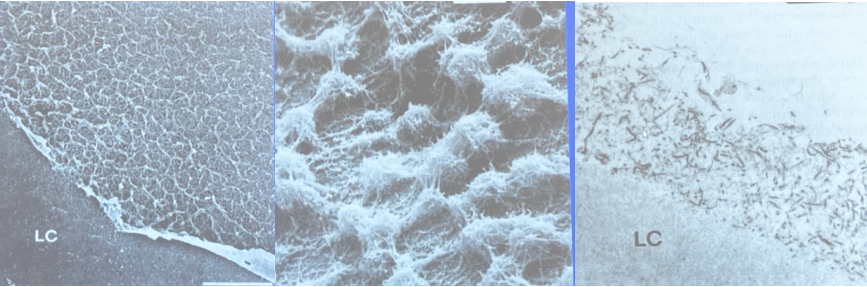

晶状体囊膜上的PXFM   角膜内皮PXFM团块  PXF黑人患者

玻璃体条带上的PXFM          角膜内皮面弥散性PXFM